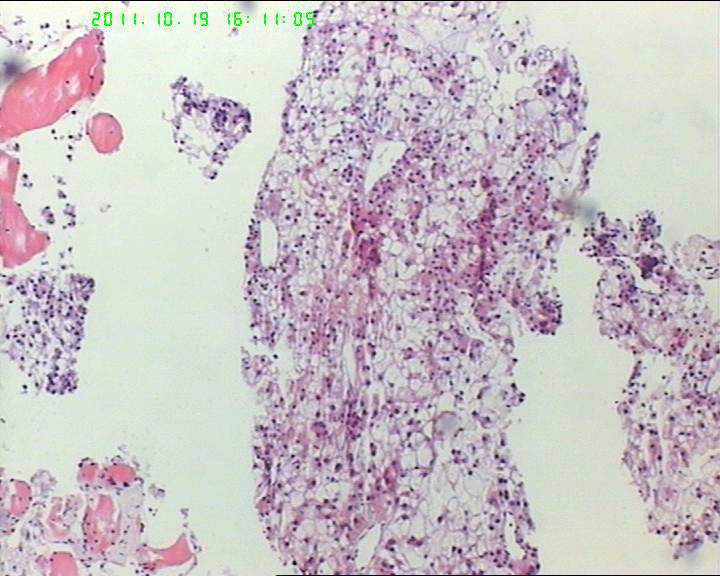

• 71岁男性肝脏占位,ct示低密灶,大三阳,afp高,转氨酶略高。该诊断什么呢?图4

图4